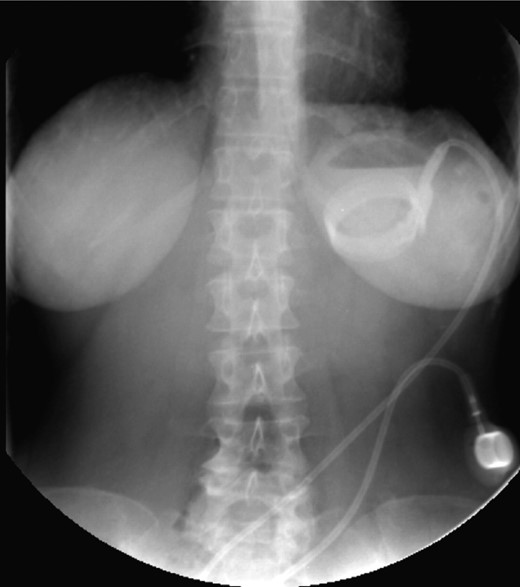

On the first day of admission, gastric banding was completely deflated. Rx abdomen showed posterior slippage of the ring (Fig. 1). Subsequently, the patient underwent rehydration therapy, 20-day total parenteral nutrition and infusion of human albumin. During that period, we examined her upper digestive tract with oral water-soluble contrast (Fig. 2) with the result of a thin liquid passage downstream of the ring and marked gastric pouch distension. Esofagogastroscopy was performed, which was negative for erosion or gastric perforation; however, it revealed a 1-cm-diameter passage through the gastric band. Despite an improvement in symptoms with partial resumption of semi-liquid intake, the patient continued to experience nausea and vomiting. For this reason, she underwent laparoscopic removal of gastric banding. In the operating room, she was placed in the lithotomy position; we placed a 10-mm optical trocar in supraumbilical region, a 5-mm one in the right upper quadrant and a 10-mm one in left upper quadrant near the subcutaneous tank. After lysis of adhesions between liver and stomach, the intraoperative picture showed a banding displacement, confirming posterior slippage of the banding and its sliding back to the level of previous gastro-jejunal anastomosis. Ascitic effusion due to dysproteinemia was reported. A methylene blue test showed no gastric perforation. After this procedure, the patient started to resume liquid intake in the first postoperative day and food intake in the second postoperative day, with complete resolution of vomiting and nausea. Then, she was discharged with the advice of an appropriate diet and invited to attend a recall visit 10 days later. In subsequent follow-up, the complete resolution of clinical symptoms was confirmed together with an improvement of the biohumoral picture.